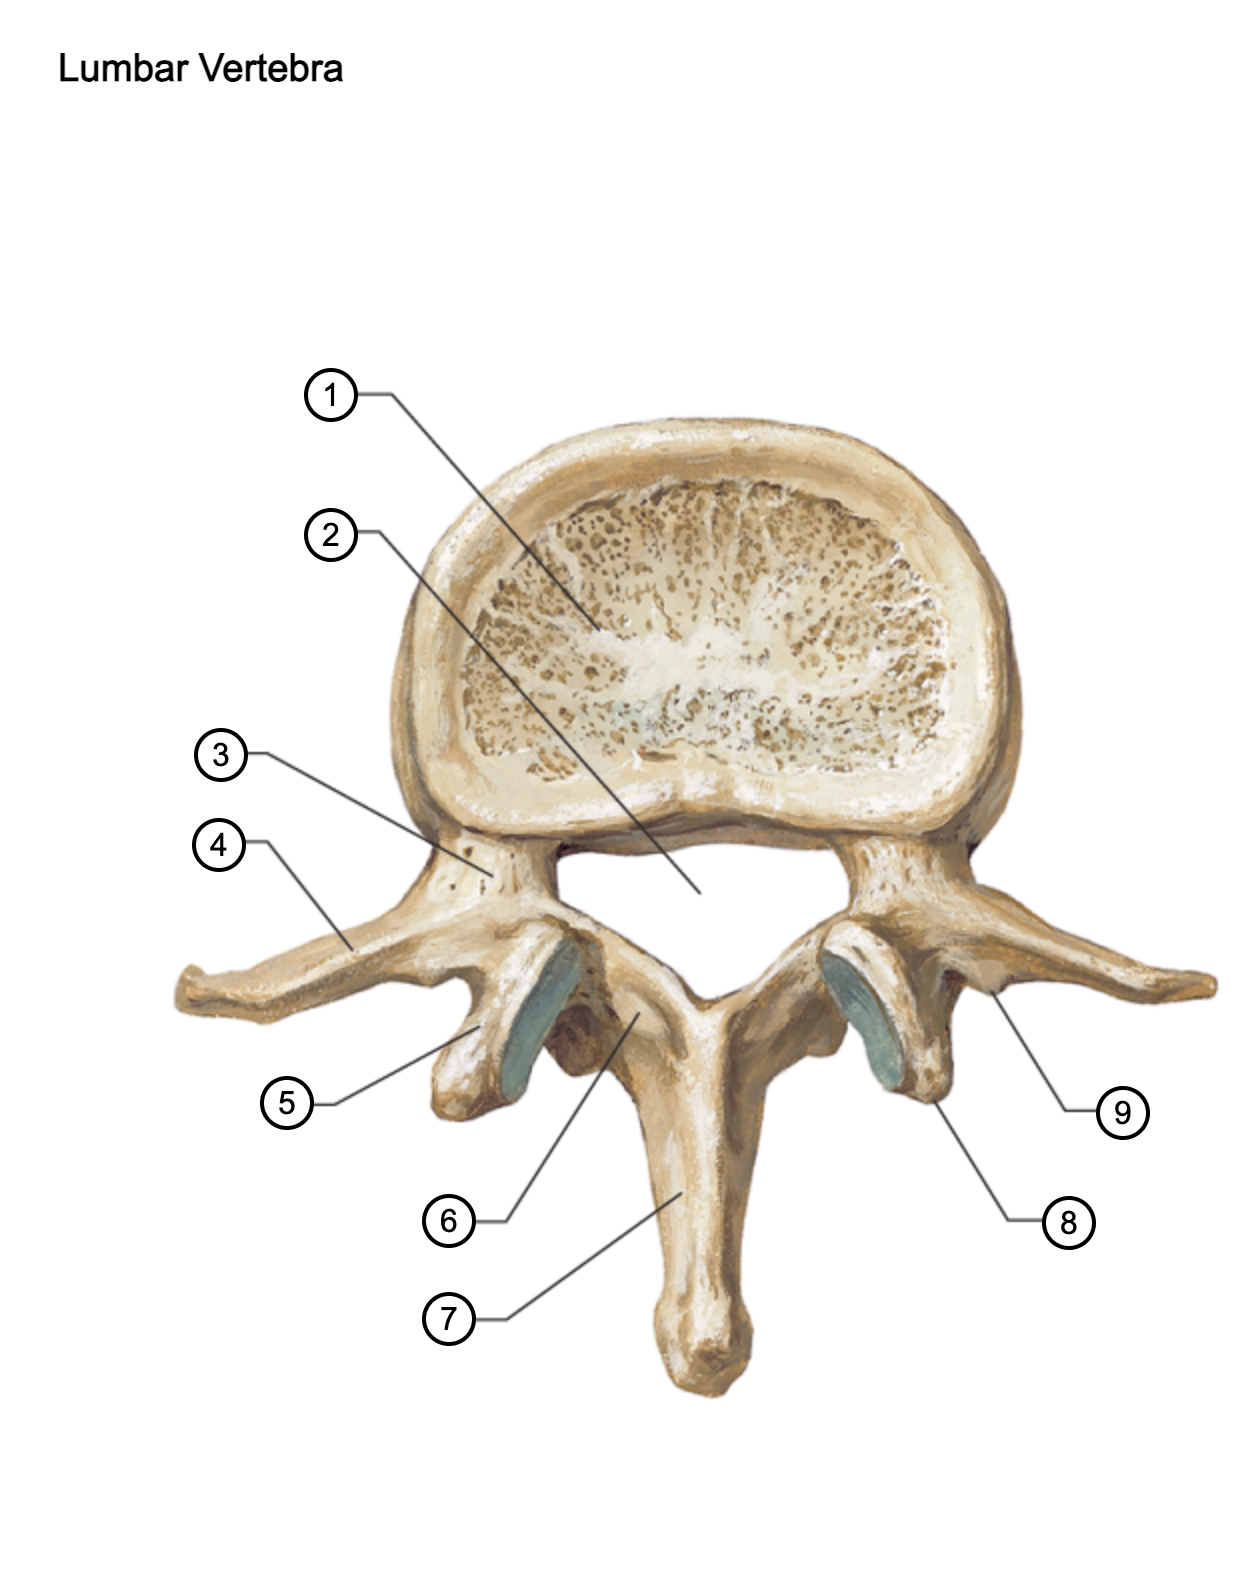

1

vertebral body

2

vertebral foramen

3

pedicle

4

transverse process

5

superior articular process

6

lamina

7

spinous process

8

mammillary process

9

accessory process